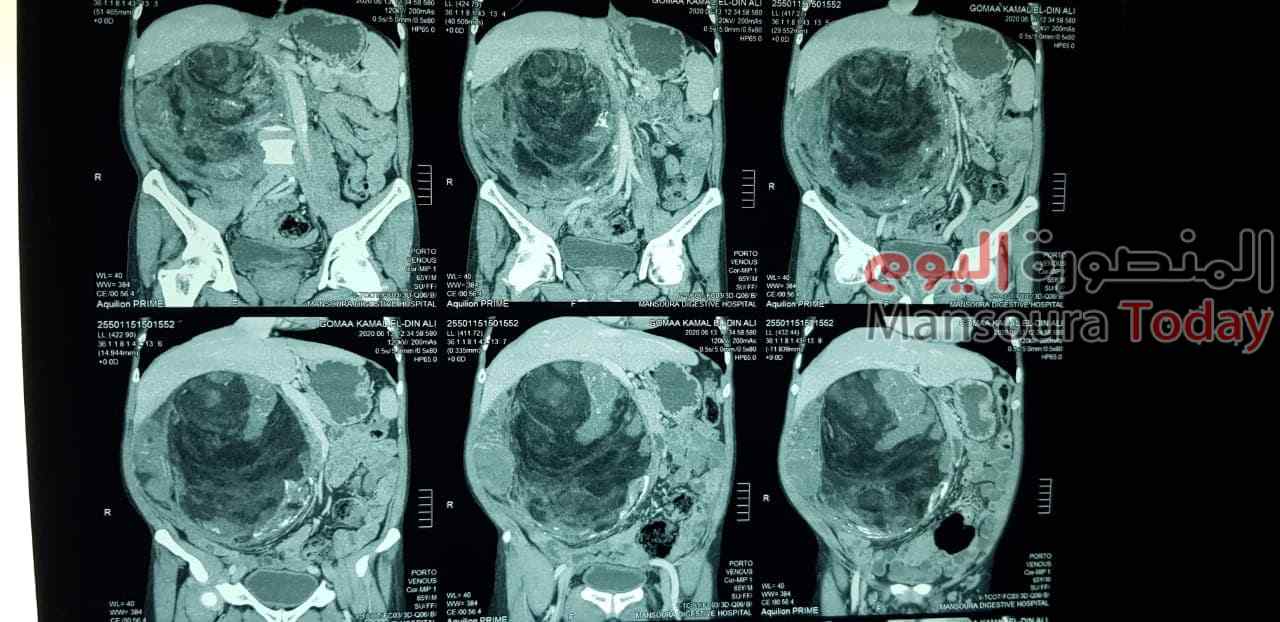

وأشار الدكتور أمجد فؤاد أن المريض يبلغ من العمر 65 عاما من مدينة بلقاس دقهلية وكان يعانى من ورم بالبطن منذ 6 أشهر ولاحظ المريض تضخم حجم البطن من سنة تقريبا وتم استقباله بالمركز من اسبوع وتم اجراء الفحوصات الازمة والاشعة المقطعية والتى أظهرت وجود ورم بحجم كبير بتجويف البطن وضاغط على جميع الأجهزة الداخلية ، وتم اجراء الجراحة واستئصال الورم ويبلغ وزنه 6704 جرامات والمريض حالته الصحية مستقرة وسيتم عمل متابعة للمري بعد تحليل الورم لتحديد نوعه .